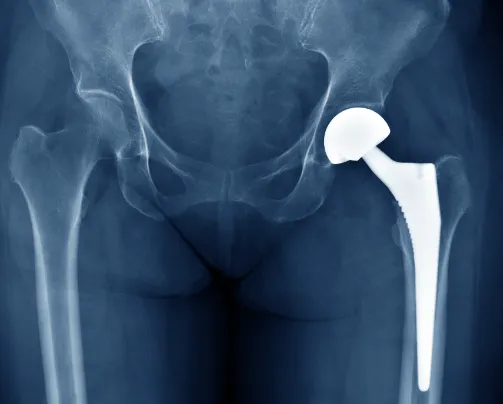

人工髖關節置換 之併發症 後遺症 建議與治療 – 松山景能物理治療所

全髖關節置換術(Total hip replacement, THR):將受損的髖關節(股骨頭與髖臼)全部更換成人工髖關節。

半髖關節置換術(Hip Hemiarthroplasty):只更換髖關節中的一部分,通常股骨頭置換。